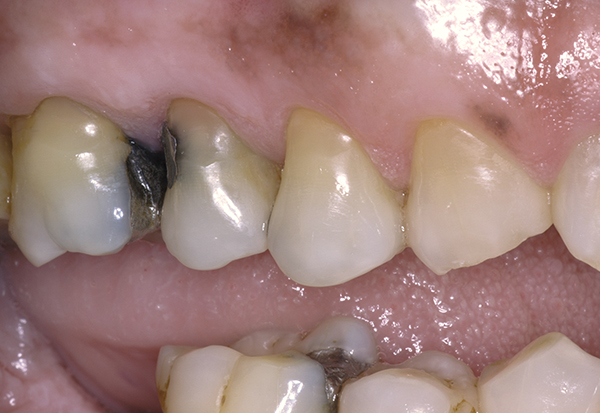

A major predisposing factor to dentin hypersensitivity is exposed root surfaces (Figure 2 through Figure 4).33 Contributors to dentin hypersensitivity include enamel loss with exposed dentin due to attrition and tooth wear caused by bruxism, occlusal habits, and parafunctional activity (Figure 5).34

(Figure 5.) Example of enamel loss with exposed dentin due to tooth attrition. The exposed dentin can exhibit dentin hypersensitivity. Treatment planned is full coverage crowns. (6.) Example of enamel loss with exposed dentin due to bulimia. Patient reports symptoms of dentin hypersensitivity. Treatment planned is full coverage crowns.